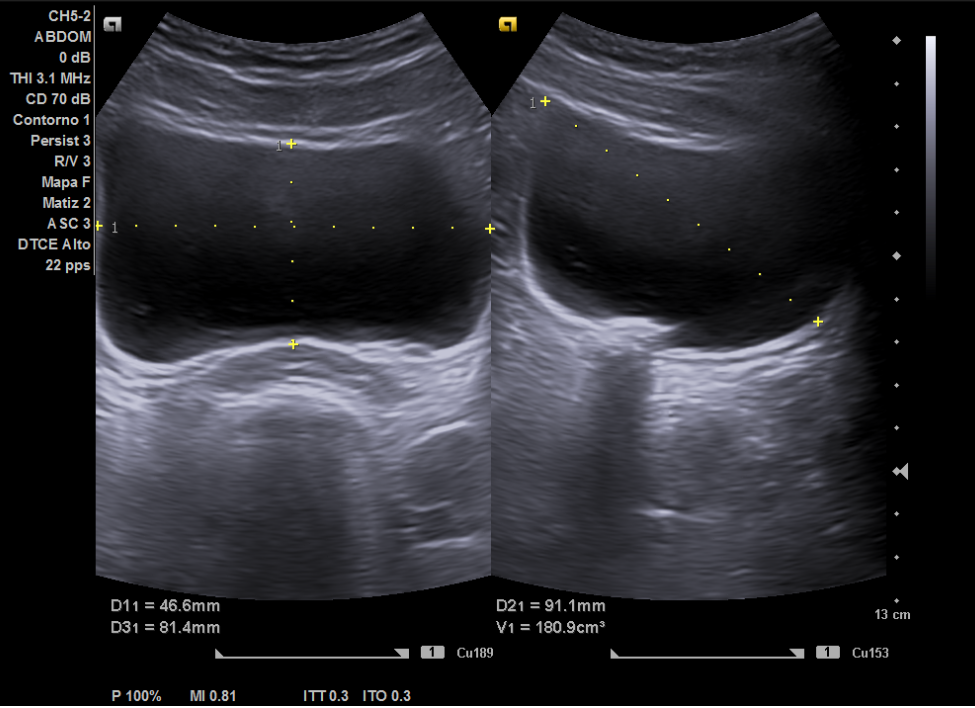

Ecografía: hígado de tamaño y ecoestructura normal, sin evidenciar masas focales. No se aprecia dilatación de las vías biliares. Vesícula sin litiasis. Páncreas visualizado parcialmente, sin evidenciar masas. Bazo de tamaño y ecoestructura normal. Los riñones son de tamaño, forma y ecoestructura normal, con buena diferenciación parénquima-seno y grosor cortical conservado, sin dilatación de vías excretoras ni clara imagen de litiasis. Vejiga distendida de aspecto normal, visualizando dudosas litiasis en las uniones vesico-ureterales.

La ecografía en el centro de salud permitió descartar dilatación pielocalicial o litiasis renal y orientó el diagnóstico hacia posibles secuelas del tratamiento endoscópico previo (STING), mejorando el manejo de la paciente en Atención Primaria. Además, aceleró los tiempos diagnósticos al posibilitar la solicitud de un TAC y una derivación más dirigida al especialista en Urología. Finalmente, cabe destacar que todo ello conlleva a la mejora de la relación médico-paciente.